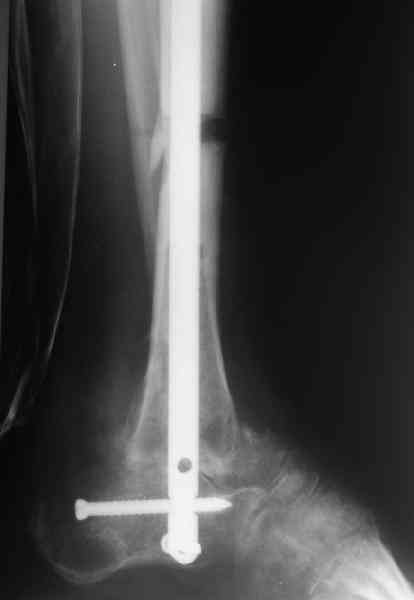

Приветствую, Павел и коллеги, ПИ> удлинения большеберцовой кости для компенсации укорочения поврежденной конечности. ПИ> В итоге: мы планируем выполнить пациенту большеберцово-пяточный ПИ> артродез в аппарате Илизарова с одновременной остеотомией берцовых В продолжение обсуждения, которое было 3 недели назад. Аналогичня операция одному нашему пациенту была сделана в конце февраля 2006. Дистракцию закончили 15 марта. На недавнем снимке нижний регенерат еще довольно хлипкий (снимок 1),

и мы не смогли обещать, что аппарат можно будет совсем скоро снять. Пациент выразил горячее желание расстаться с наружным фиксатором, даже если нужна еще одна операция. На этой неделе выполнили закрытое штифтование (впервые именно в такой ситуации) и сняли аппарат.

Аппарат был снят окончательно только после введения стержня, то есть оставалось по одной спице в проксимальном и дистальном метафизах большеберцовой кости, спицы в пятке. Фото во время рассверливания в приложении.

Стержень 12 мм, винт диаметром 6 мм, костная трубка вокруг хорошая. Перелом такого винта пока не наблюдали ни разу на нескольких сотнях

пациентов.